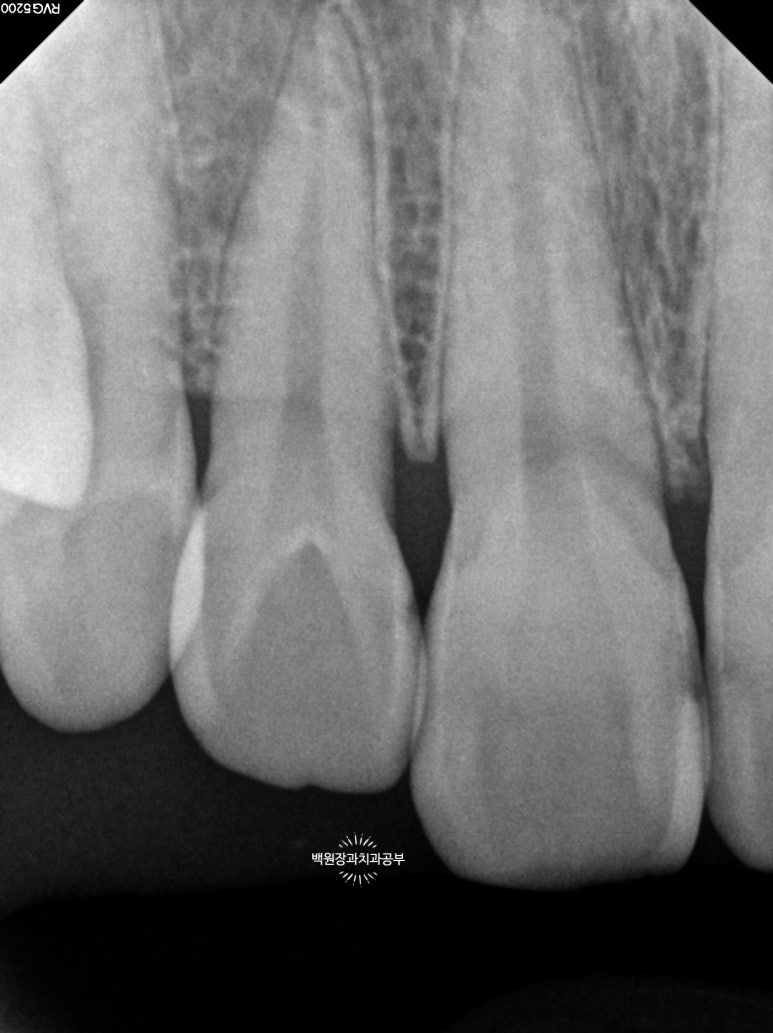

충치의 범위를 파악하기 위해 작은 엑스레이를 찍어봤어요.

Previous image Next image

총 세장의 치과용 치근단 방사선사진을 찍었고,

각 치아마다 옆면의 충치 범위를 확인할 수 있었어요!

까맣게 물들듯 보이는 곳들이 충기가 있는 곳입니다.

치과용 엑스레이 판독을 일반 사람이 하기는 힘드니깐,

제가 보기 쉽게 표시해 드릴께요!!

노란색으로 표시해 놓은 곳들이 옆면 충치가 있는 곳들이에요!

눈으로 확인하는 시진과 방사선 검사를 종합해서 합집합이 되는 부위를 모두 치료하면 됩니다.